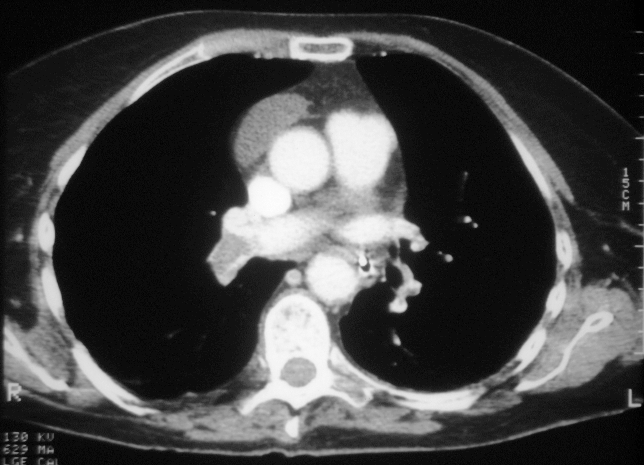

EMBOLIA PULMONAR

Cóagulos observados por Tomografía Computarizada